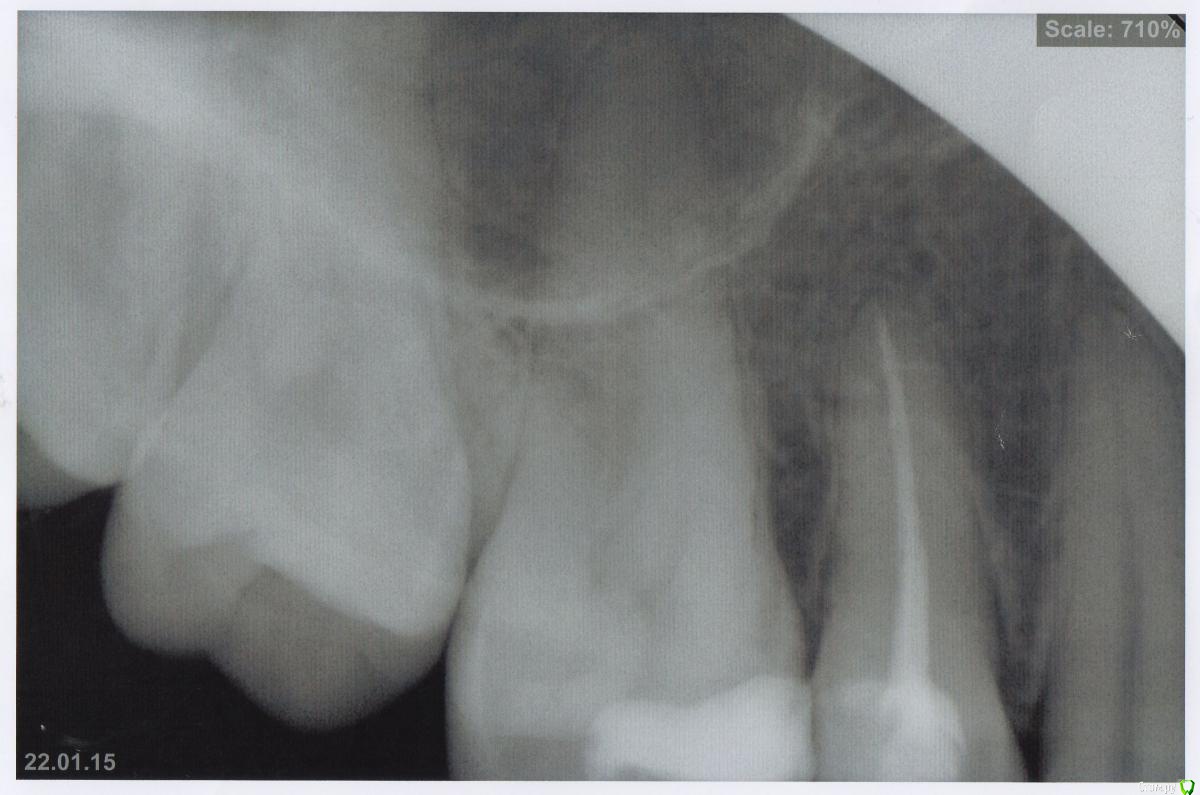

Анна Минск Опубликовано 19 октября, 2015 Поделиться Опубликовано 19 октября, 2015 Здравствуйте, уважаемые доктора и участники форума! Прошу у вас помощи, т.к. отчаялась понять, что проиходит с моей верхней челюстью. Зуб пятый сверху справа был пролечен, депульпирован и запломбирован лет 10 назад. С тех пор периодически возникали тянущие боли в области 4-6 зуба, помогали просто полоскания и обезболивающие и боль через несколько дней стихала. Около полугода назад вместе с болями между пятым и шестым сверху справа зубом появился твердый бугорок, похожий наощупь на костное образование. Ходила к врачам, они щупали и говорили, что это мое индивидуальное, видимо, строение челюсти. Но я точно знаю, что раньше его там не было! Он расположен высоко на десне снаружи на стыке челюсти и щеки, между пятым и шестым зубом. Сделала снимок этих зубов, по снимку сказали, все в норме, каналы пролечены нормально. Сделала КТ, по КТ в пятом хронический апикальный (фиброзный) периодонтит. Врачи сказали, лечения не требует. Но все-таки вскрыли пятерку и перелечили каналы. Через месяц, примерно в июле, появилось уплотнение на внутренней стороне челюсти в районе пятого, шестого зуба. Оно довольно большое и твердое, визуально не определяется, отека вроде тоже нет. Просто какое-то твердое большое образование,которое начинается сразу возле зубов и переходит на небо.Сейчас уже неделю меня мучают боли в районе верхней челюсти и этих зубов, 5 и 6, болит не только челюсть, но и висок, шея. Четыре дня назад поднялась температура. Врачи смотрят снимок и говорят, что все в норме, КТ на диске смотреть отказываются, говорят, нам достаточно заключения. Только хирург в поликлинике предложил удалить пятерку. Я уже согласна удалить, если знать наверняка, что это поможет мне избавится от изнуряющих болей. Волнуюсь, что какой-то патологический процесс там происходит, а что делать не знаю. Пожалуйста, помогите мне, может кто-то подскажет хорошего врача в Минске, который сможет разобраться, что там у меня происходит, буду очень благодарна. Ссылка на КТ https://yadi.sk/d/gAfKorvCjjuPP Ссылка на комментарий

Гарриевич Опубликовано 19 октября, 2015 Поделиться Опубликовано 19 октября, 2015 По прицельным снимкам никакой кисты нетСкорее всего проблема в застревание пищи между 5 и 6 зубом. Позже посмотрю ваше кт Ссылка на комментарий

krokomot Опубликовано 19 октября, 2015 Поделиться Опубликовано 19 октября, 2015 на кт ничего определенного не видно, возможно в какомто из зубов воспаление нерва, надо проверить на витальность эубы с этой стороны. Ну и нужен очный осмотр. Кстати только у меня на кт открывается только панорама? Ссылка на комментарий